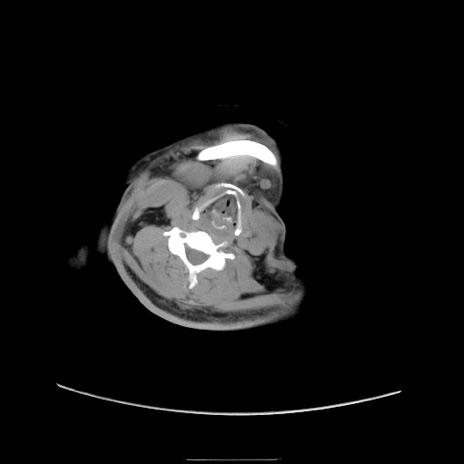

症例22(横断像)

【症例】50歳代男性

【主訴】腹痛

【現病歴】AVMからの被殻出血のため回復期リハ病棟入院中。 本日午後3時頃急に下腹部痛が出現した。

【既往歴】AVM、被殻出血、虫垂炎、高血圧

【身体所見】意識晴明、左半身不全麻痺、会話の理解は良好、36.5°C、腹部:膨隆、全体に板状硬、下腹部正中に圧痛点あり、反跳痛-、筋性防御不明、右下腹部にope scar

【データ】WBC 9400、CRP 0.06